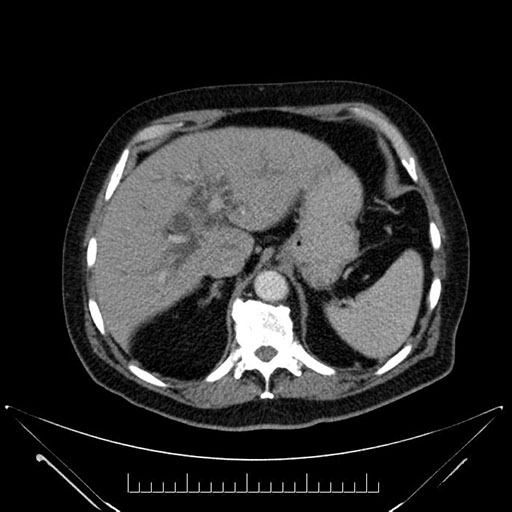

Whipple (pancreaticoduodenectomy) [case 7]

Axial - stented